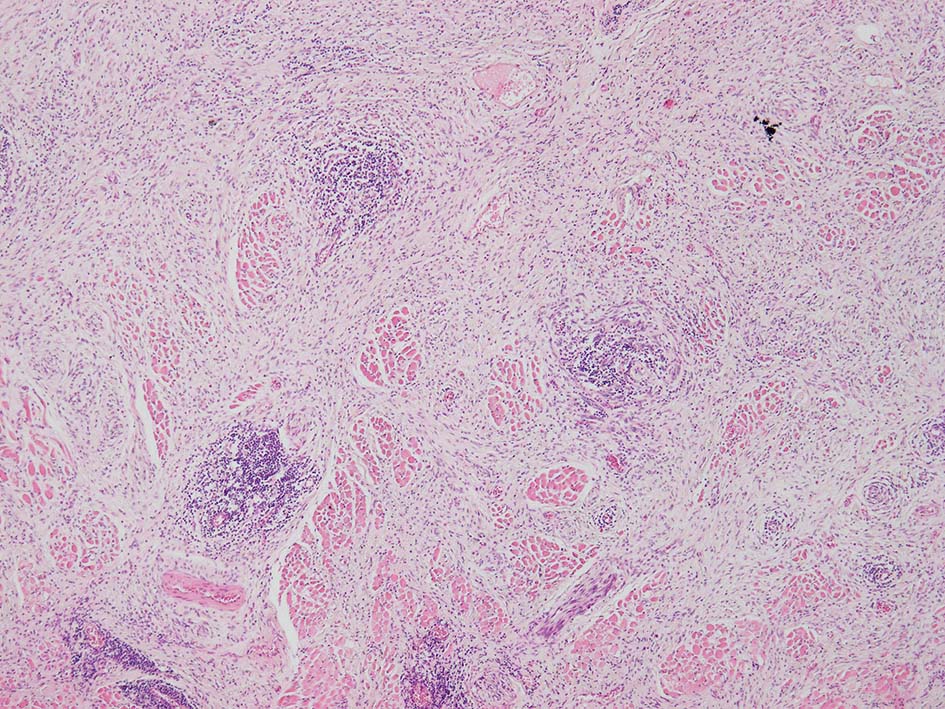

紡錘形異型メラノサイトが著明な間質反応(desmoplasia)を伴い増殖する特殊な色素性病変。*1. desmoplastic neurotropic melanomaは, desmoplastic melanomaのうち神経向性(neurotropism:神経周囲侵襲像)がめだつものでReedら*2が最初に報告した。

いずれも腫瘍細胞の異型性が乏しく, 背景の間質反応がめだつこと, メラニンの存在が目立たないことが特徴である。

病理組織所見*4

リンパ濾胞が細血管周囲に形成され, この部分に異型といえる細胞が増加している(S100+)

再発腫瘤病変の組織像